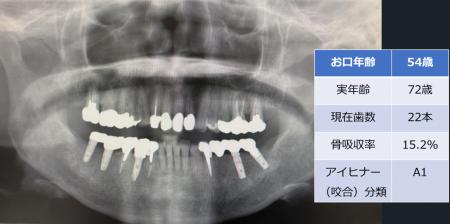

「お口年齢AI」は、歯科パノラマエックス線画像から、現在歯数、インプラント数、アイヒナーの咬合分類、歯槽骨吸収量などの抽出したデータと、生年月日・性別の情報から、「お口年齢」を算出するシステムとなっています。

[画像2:

https://prcdn.freetls.fastly.net/release_image/73133/7/73133-7-8727f0a4a417fe5cd42bb3d0a4f3a5c6-3861x2022.jpg?width=536&quality=85%2C75&format=jpeg&auto=webp&fit=bounds&bg-color=fff ]

本システムでは、生活習慣病である歯周病に関連する歯槽骨吸収量も加味して判定しており、また抜歯後にブリッジやインプラント治療を行った場合などは、顕著に「お口年齢」が若年指標として算出されます。